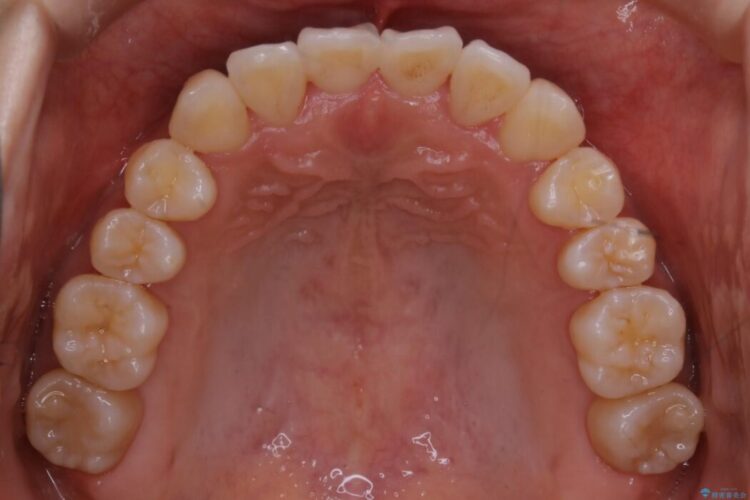

前歯のガタガタを気にされて来院されました。

検査の結果、骨の厚みに余裕がないことが判明しましたので、幅の拡大と歯の側面を削るIPRでは歯周病に対する不安を拭いきれないと判断しました。

よってマイクロインプラントを用い、奥歯から順番に遠心移動させることによってスペースを確保することにしました。

歯を後方に移動させてスペースを確保する場合、マウスピースの装着時間に加えて装着時の適合度が良い状態に保たれているかが鍵となります。

歯は戻ろうとする力が強いためマウスピースの装着をしっかりしていただけなかった場合は、作り直しや治療の長期化につながってしまう可能性があります。